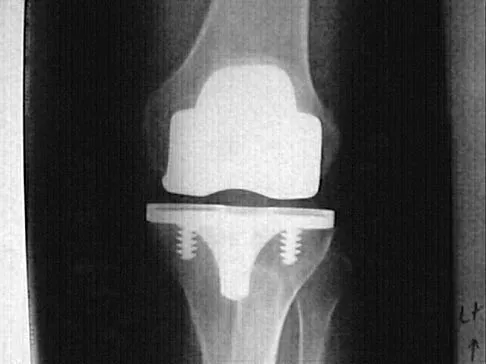

Question 12 High Yield

Figures 57a through 57c show the radiographs of a patient who has pain, discomfort, and a popping sensation localized to the posterior aspect of the knee after undergoing primary left total knee arthroplasty 6 months ago. Examination reveals that the patient is able to ambulate without a limp. There is no significant swelling, erythema, or effusion. Range of motion is 0 degrees to 115 degrees, and a palpable crepitation or snapping is detected at the posterior lateral joint line. What is the most likely diagnosis?

Detailed Explanation